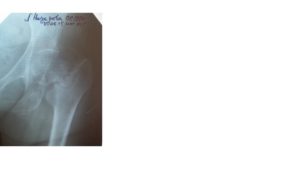

Основной метод диагностики переломов в подвертельной области — рентгенография. Процедура позволяет с большой точностью выявить место перелома и его характер. В отдельных случаях может потребоваться компьютерная томография, позволяющая обнаружить нарушение мягких тканей и сосудисто-нервных пучков.

Рис. 2 Рентгенограммы тазобедренного сустава. а. межвертельный перелом бедренной кости; б. чрезвертельный перелом бедренной кости.

Диагноз ставится на основании рентгенографического исследования. Если картина повреждения и особенности расположения отломков недостаточно ясны, то проводится компьютерная томография тазобедренного сустава.

Этот метод позволяет получить послойное изображение проблемной области, точно оценить количество фрагментов кости, направление их смещения.